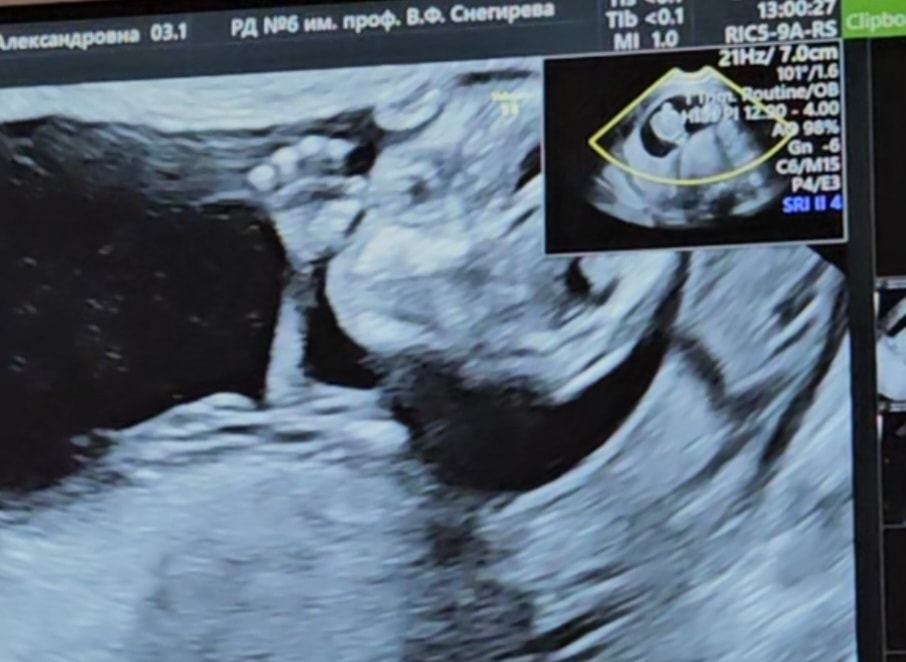

Я БЕРЕМЕННА !В пятницу 25.07 на 12н2д прошли первый скрининг! Все хорошо, сын растёт по сроку, на узи показал себя со всех сторон!) Делала по омс в род дом6)

Оставлю фото на память!! Мой малышарик, пальчик большой сосёт)))